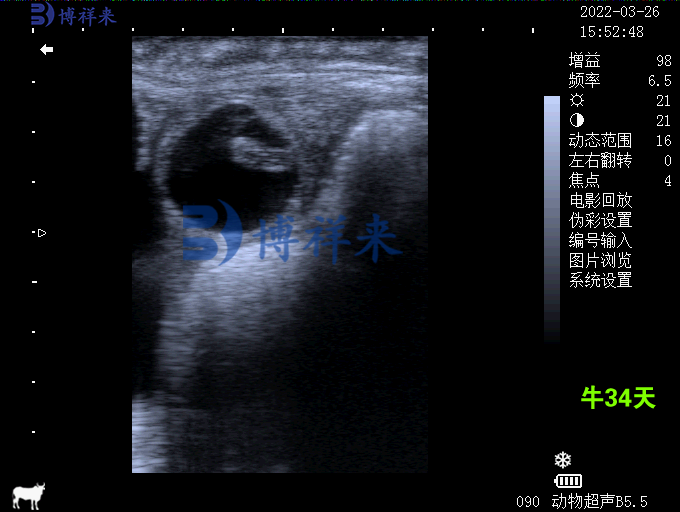

1. 高精度成像,早期妊娠检测

博祥来B超机配备高清晰度探头与图像增强技术,可在受孕后18-25天内对猪、牛、羊等动物进行早期妊娠检测。这大大缩短了等待周期,有助于尽早识别空怀母畜并重新配种。